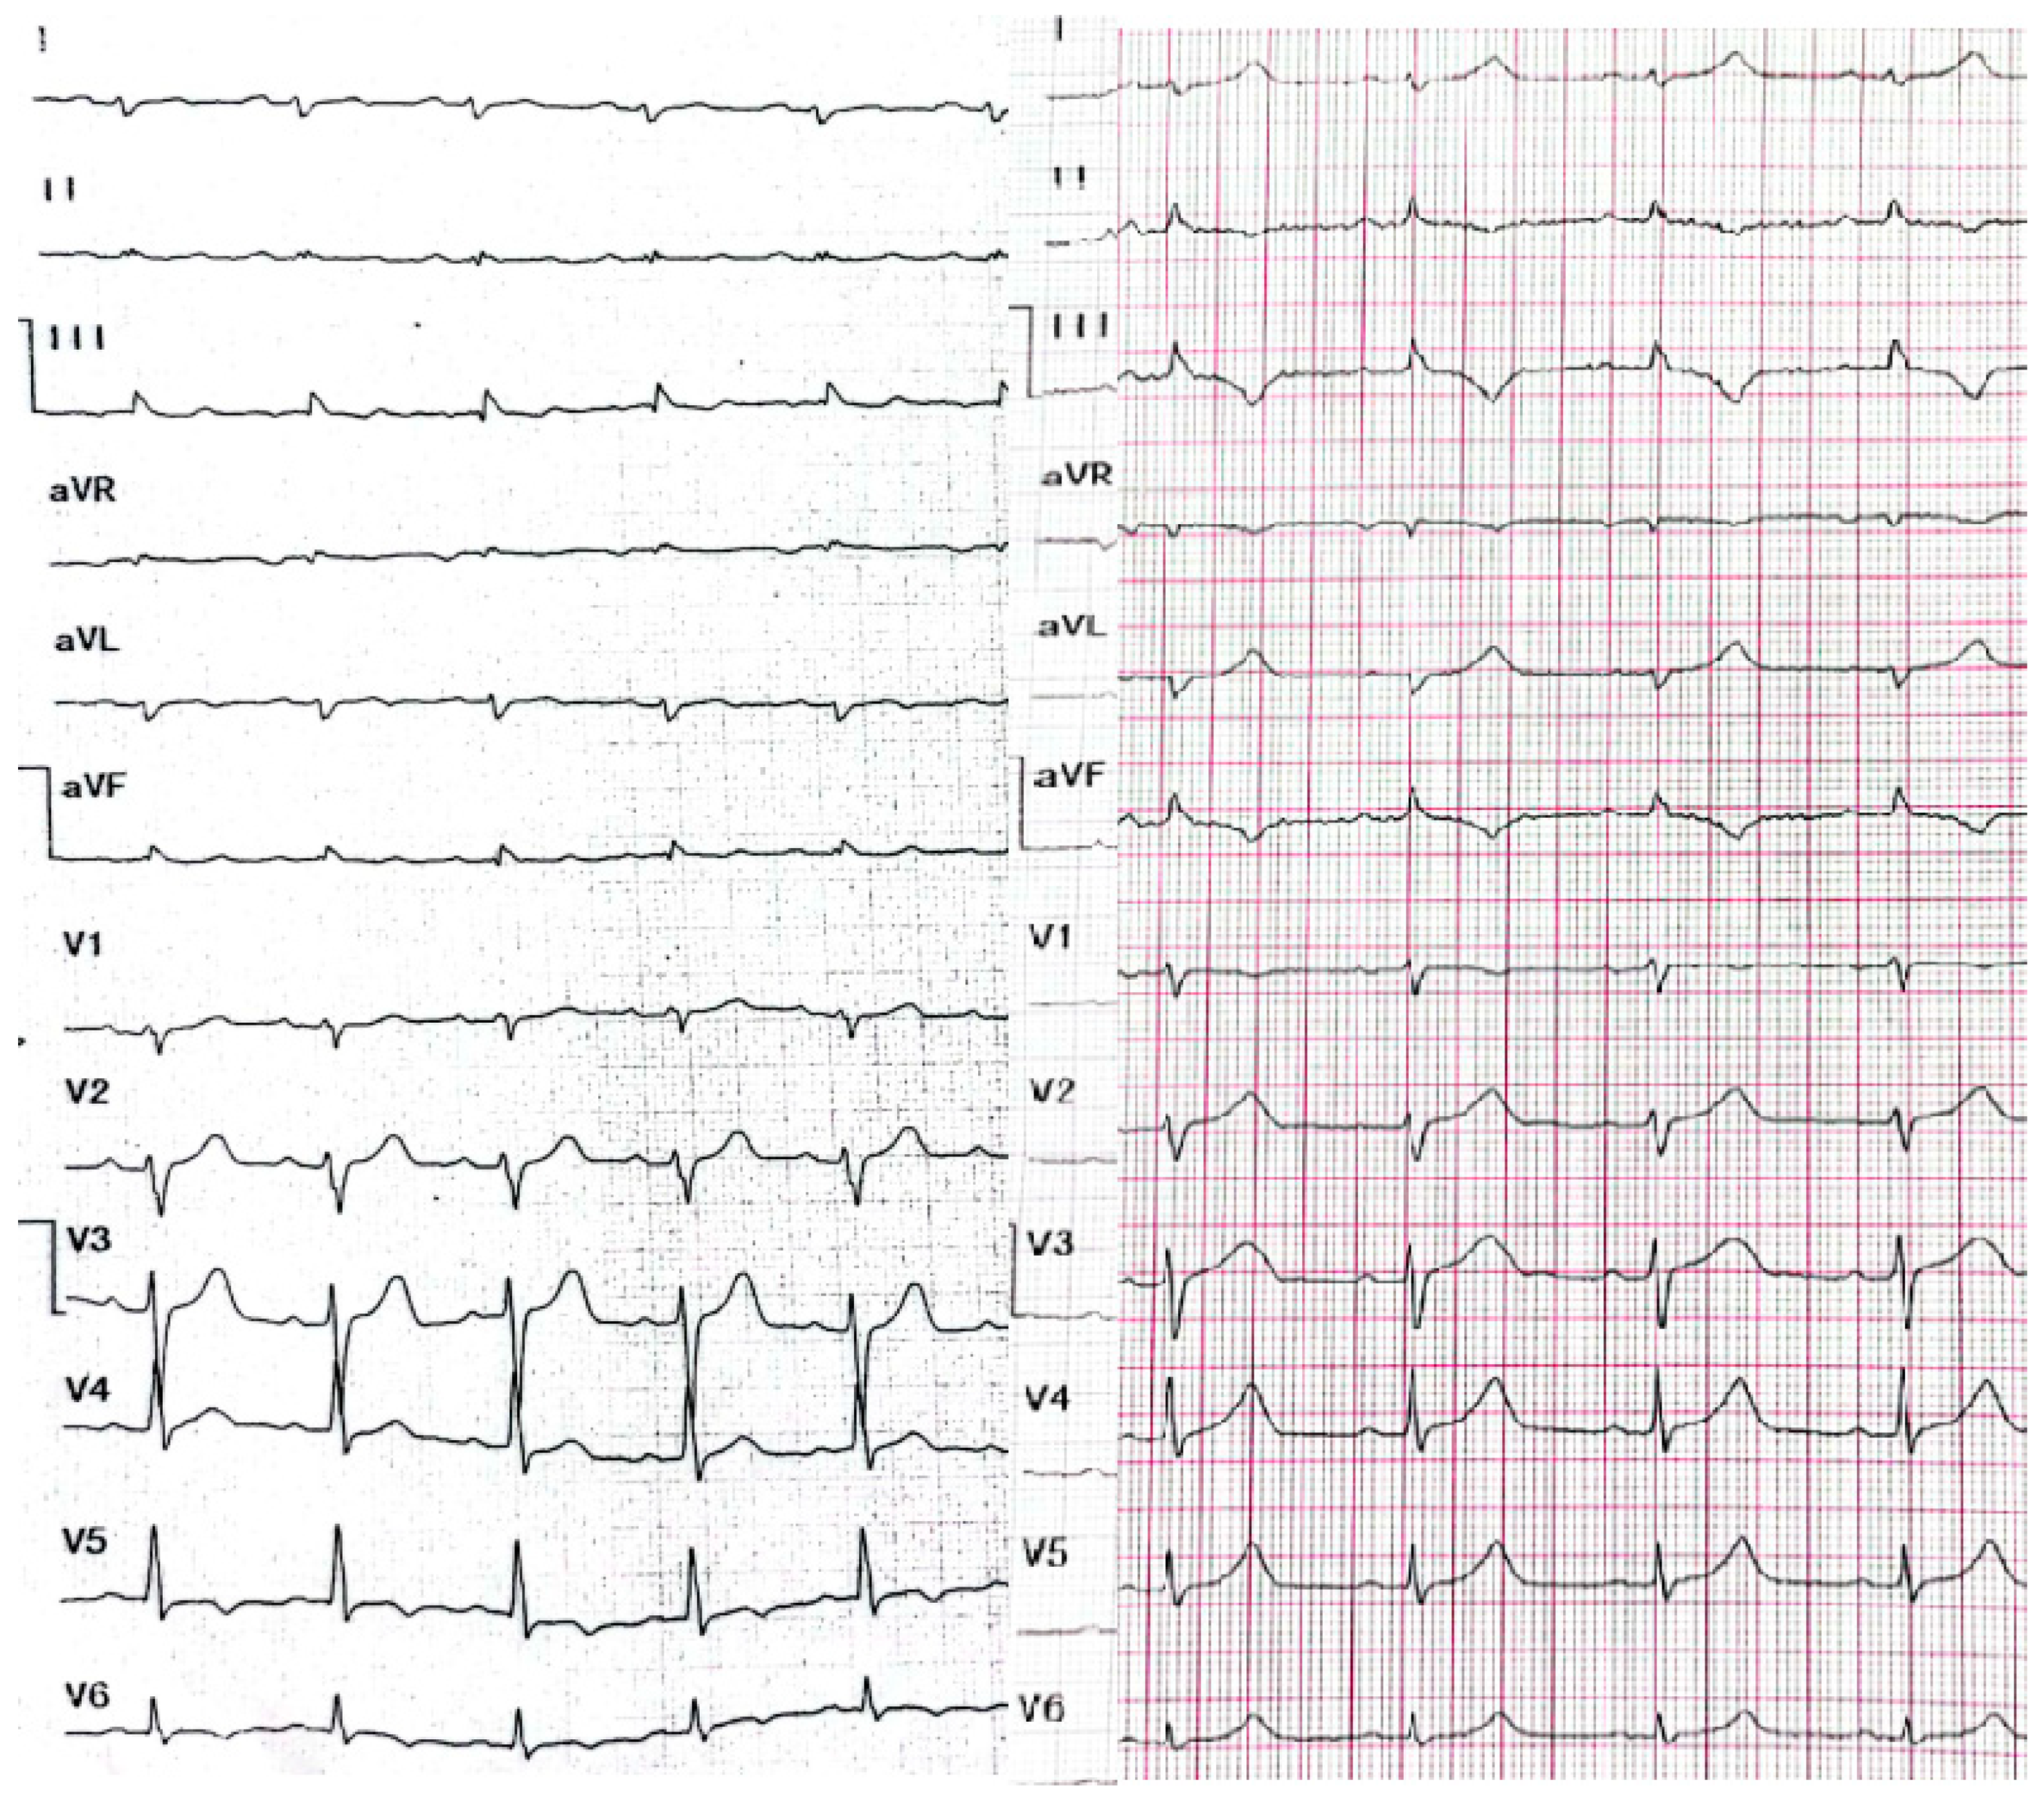

2. Case Presentation